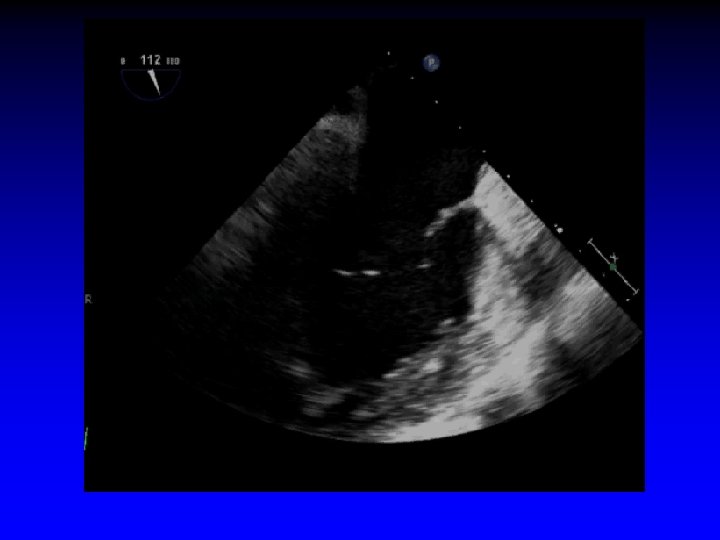

Case 1 Ruptured cords P 2

1. 6 cm +. . . + Gastric short-axis view (PSR view)